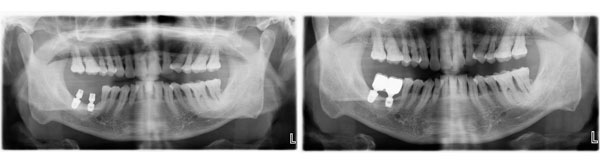

患者右下两颗后牙种植修复